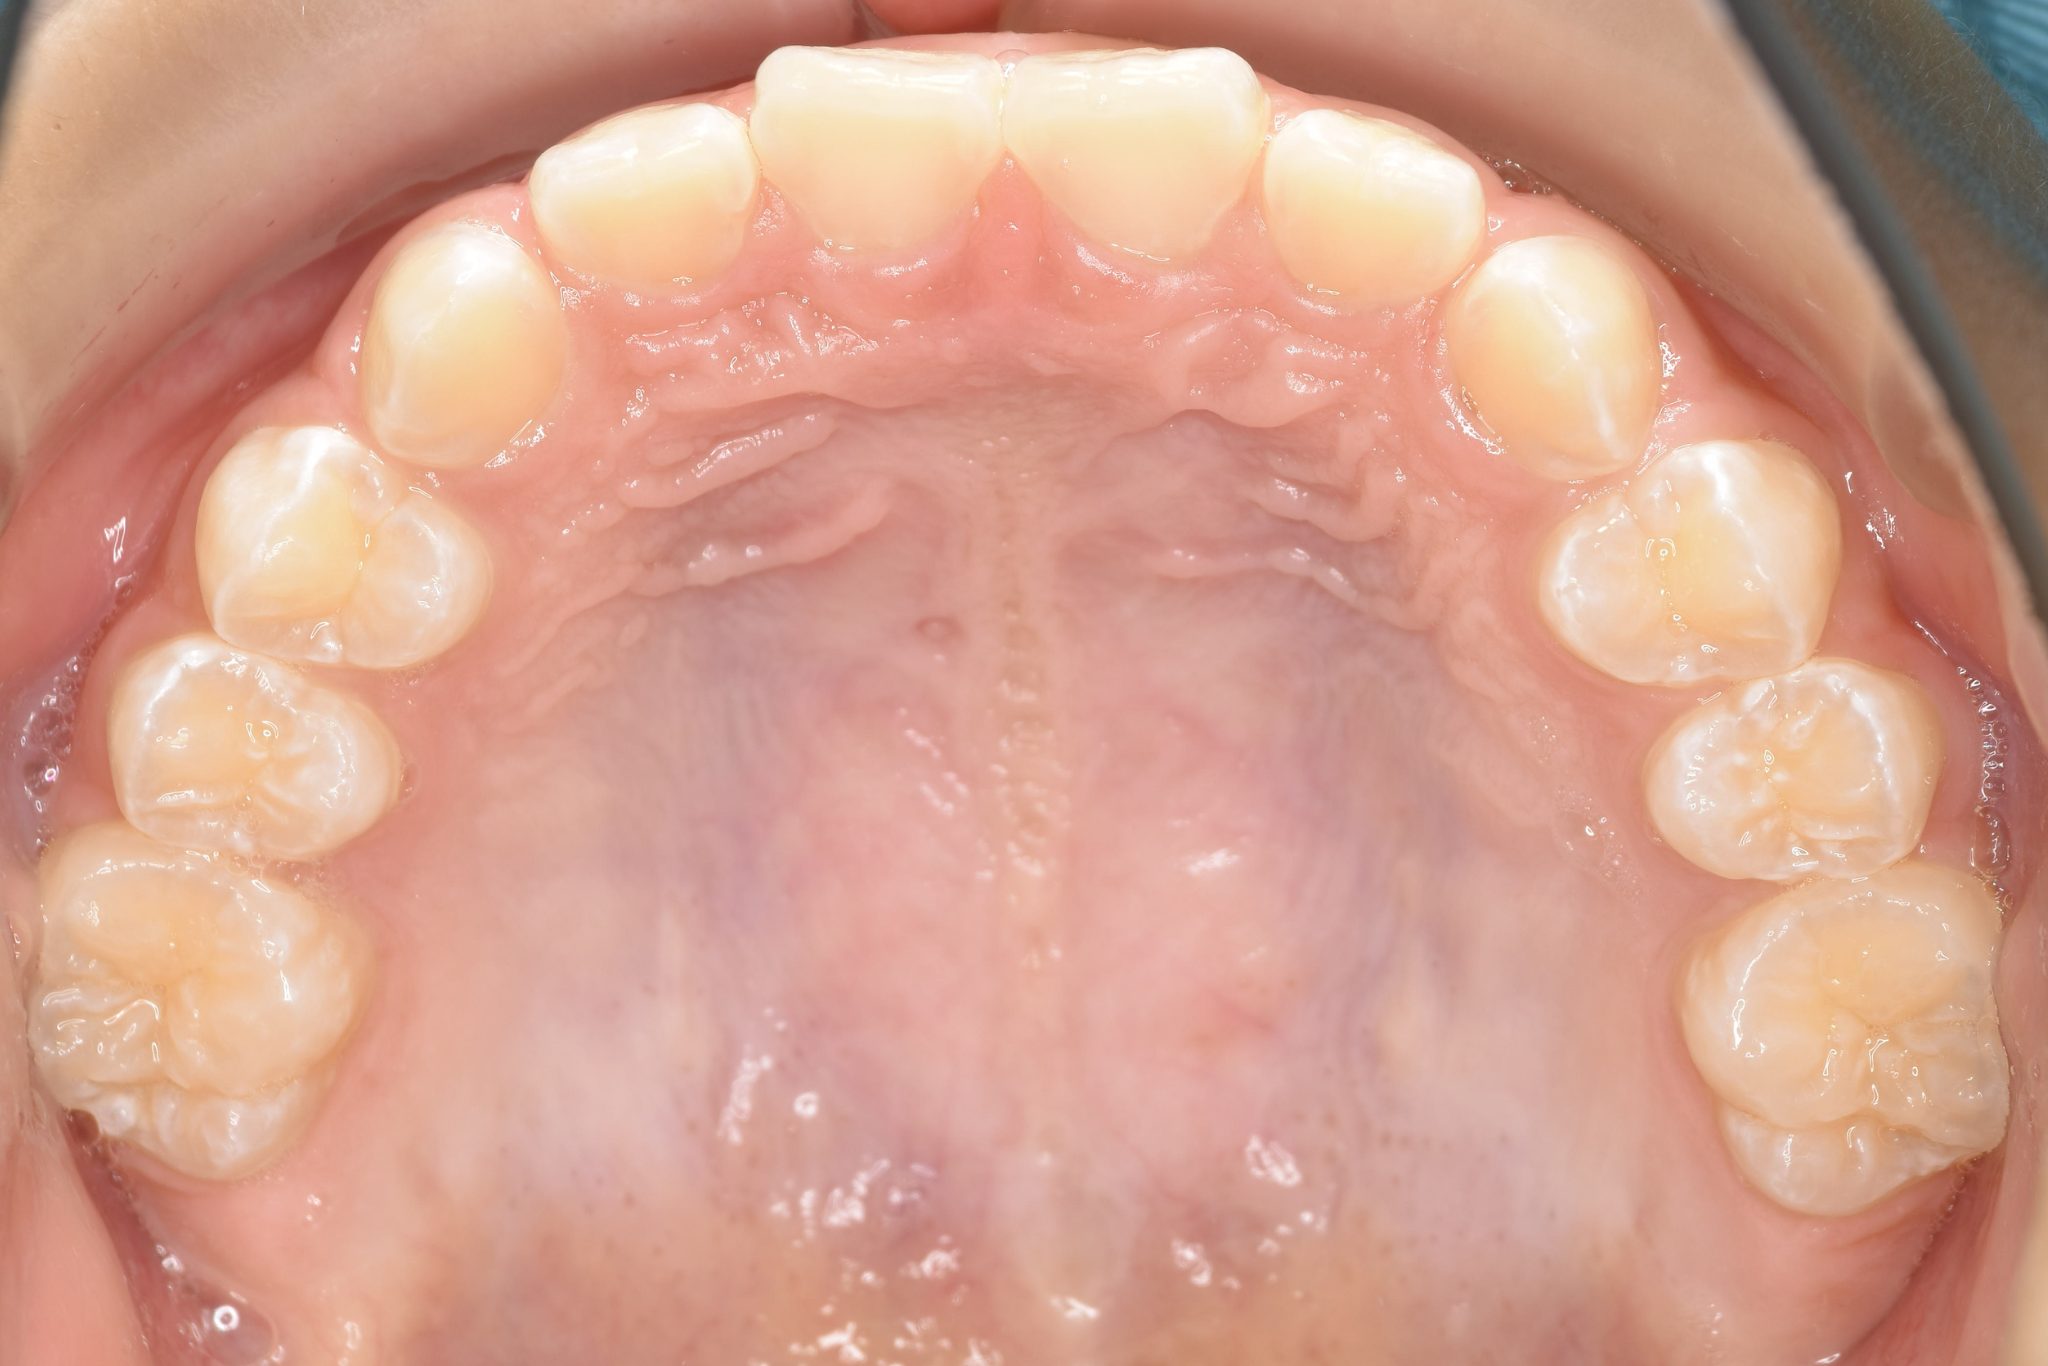

ビフォー

子どもの矯正治療|症例_858